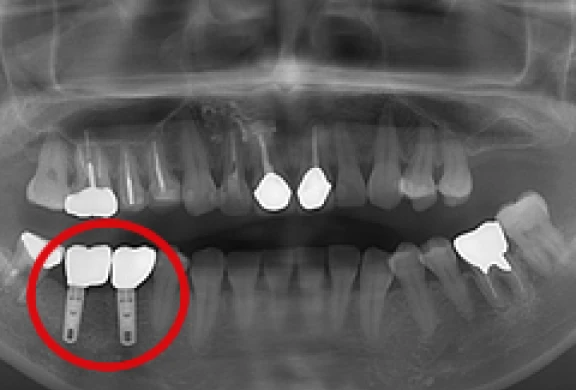

歯科用CTによる精密診断を行い、お口の中の状態をしっかり把握させていただいた上で、適応のある方は院内にてインプラント治療を行います。

歯を失って再びご自身の歯のような噛み心地をご希望の方は、ご相談いただきたいと思います。

- 歯科用CT(タカラベルモント社BEL-X(ベルクロス))を設置しています。当院で撮影・画像診断を行い、院長自らが手術を行いますので、安心してご相談下さい。

- 当院ではHA(ハイドロキシアパタイト)インプラントを採用しています。

インプラントの埋め込み

上部構造の装着

パノラマ

歯間部のインプラント

(上部構造の装着)

(2本)

(2本、上部構造の装着)